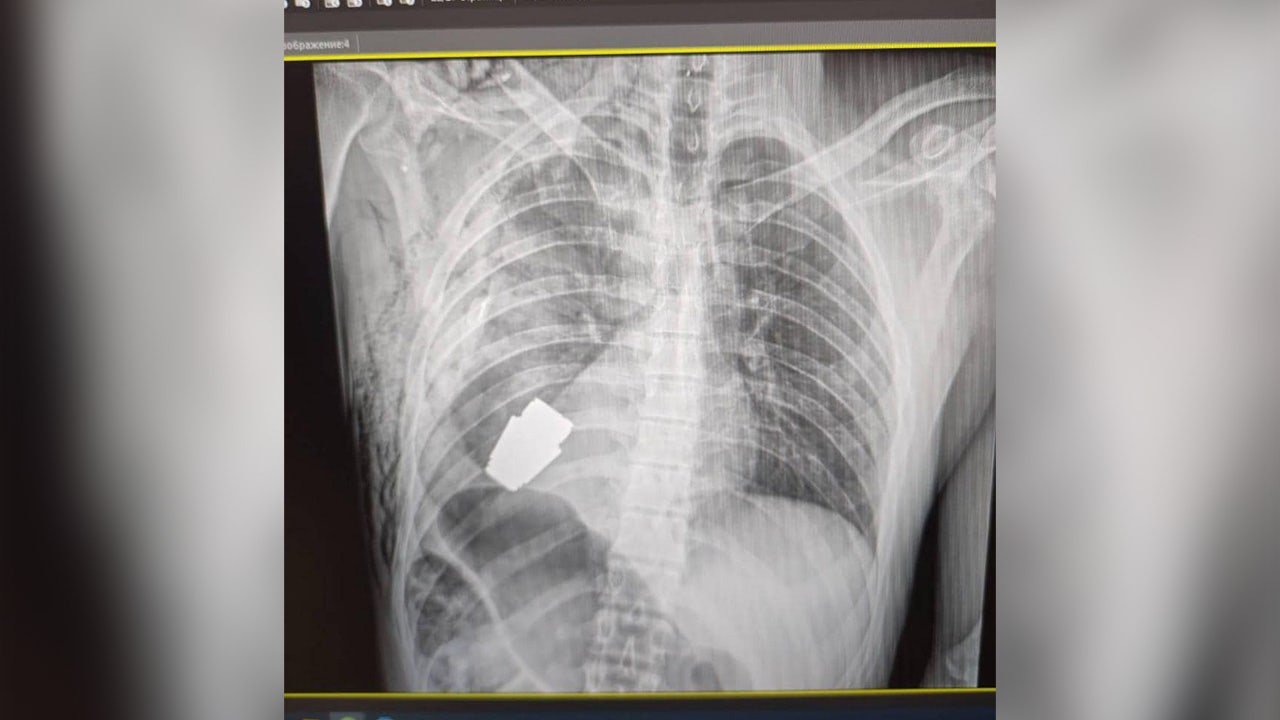

X-ray showing a foreign object inside the body of an unidentified Ukrainian soldier. (Hanna Maliar, Ukraine’s deputy defense minister.)

Hanna Maliar, Ukraine’s deputy defense minister, posted images to her Facebook page showing an X-ray image of a foreign body lodged near the heart of an unidentified soldier.

That X-ray image was placed next to another one showing what appeared to be a surgeon donning bloody gloves and holding the live grenade after it was removed.